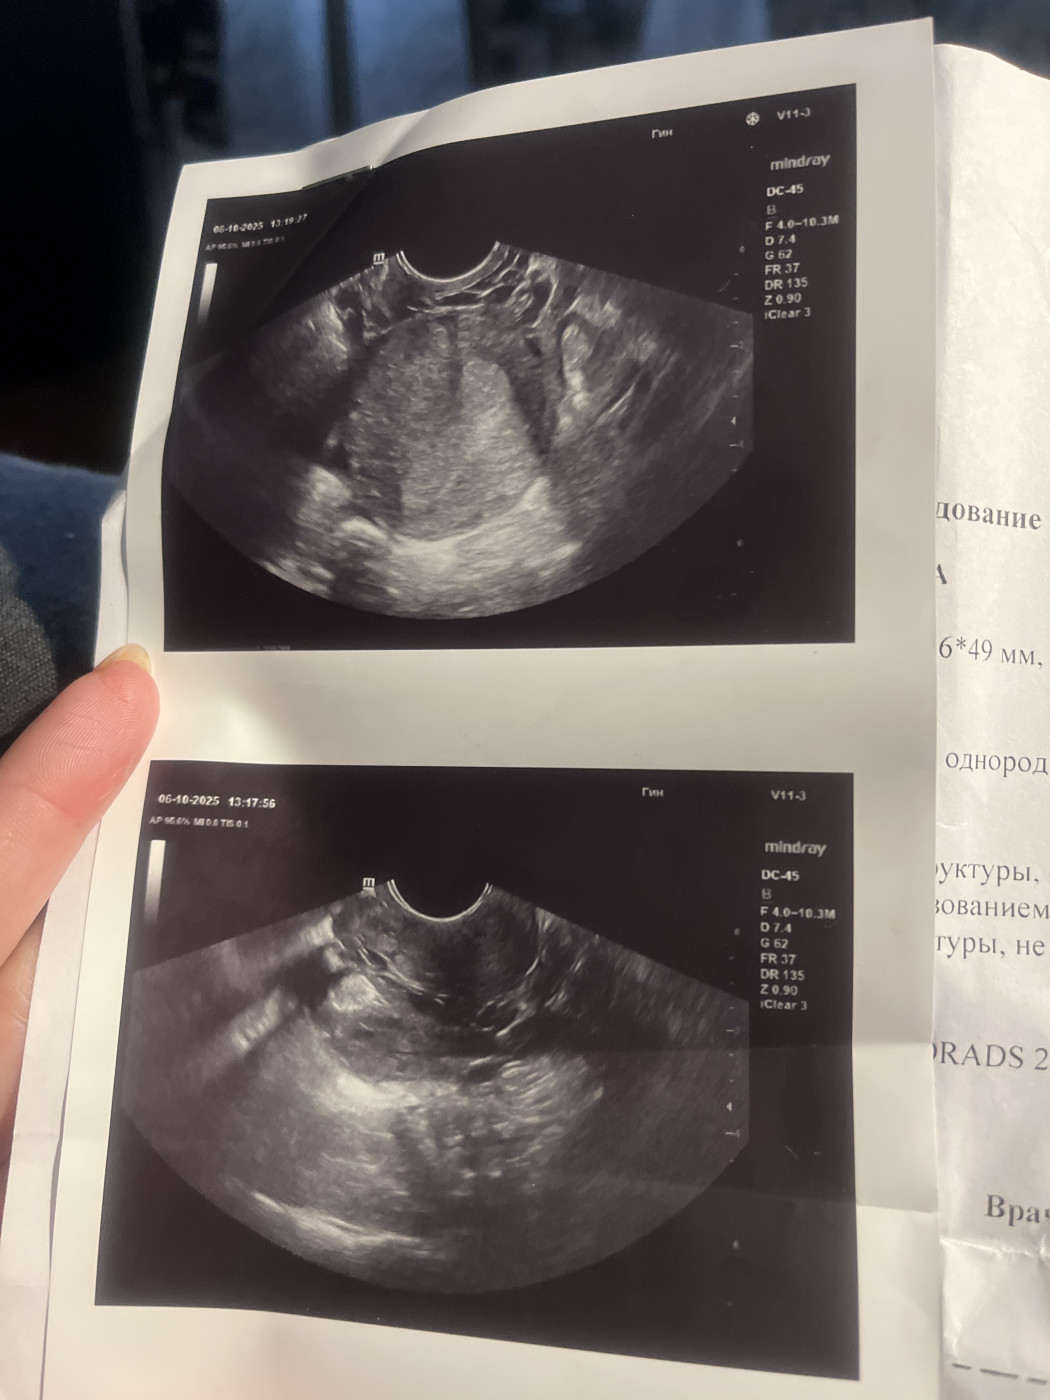

Внематочная беременность?   1 ответ

Последняя менструация 25.08 по 30.08

Была задержка но боли были такие как при менструации я сделала тест и от 04.10 показало 2 ярких полоски. Записалась на УЗИ И сдала ХГЧ от 05.10 результат 492 мМЕ/мл на УЗИ ничего не увидели. 08.10 я опять пришла на УЗИ ничего не видно и сдала ХГЧ. Хгч от 08.10 показало 700 мМЕ/мл. Поставили подозрение на внематочную…